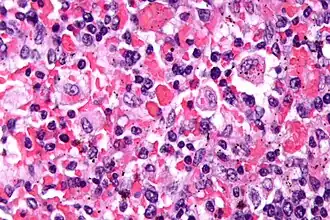

| Microfotografia mostrando eritrócitos fagocitados por macrófragos em paciente com linfo-histiocitose hemofagocítica. Coloração H&E. | |